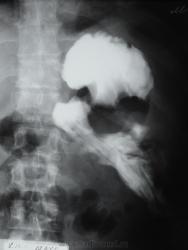

молодой мужчина, прооперирован по поводу панкреонекроза и флегмоны забришины.

направлен на скопию исключить свищ желудка. Выпил до 200 мл водорастворимого контрастного вещества (омнипак +вода). Ваше мнение коллеги?

1. Схему своего видения проблемы представляю.

2.Затек, судя по всему - есть (очевидно по задней стенке)

3. Крайне необходимым было производство боковой рентгенограммы, раз уж Вам его доставили в кабинет.